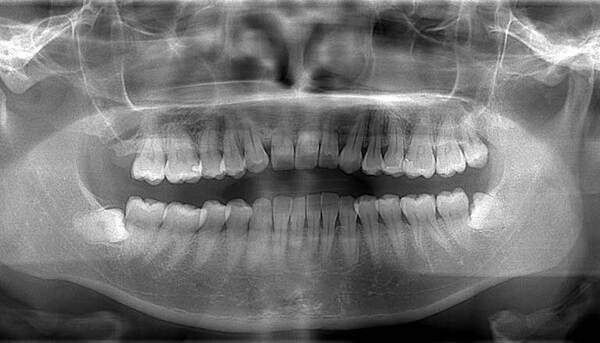

麻布十番歯科で虫歯の親知らずのレントゲン画像のイメージ

上顎はしっかり親知らずがはえています。下顎は右側は(青色)しっかりはえていますが、虫歯になっています。下顎の左側(赤色)は斜めにはえています。またこちらも虫歯になっています。

この場合、右側上下は残して、左側上下は抜くことがファーストチョイスになります。しかし、左上の6番目の歯(緑色)は根の治療をしており、虫歯にもなっていそうですので、左上の親知らずは移植歯として残しておいても良いという判断になります。

もちろん、患者様が移植は考えてなく、抜歯をしたいということであれば、抜歯を行います。